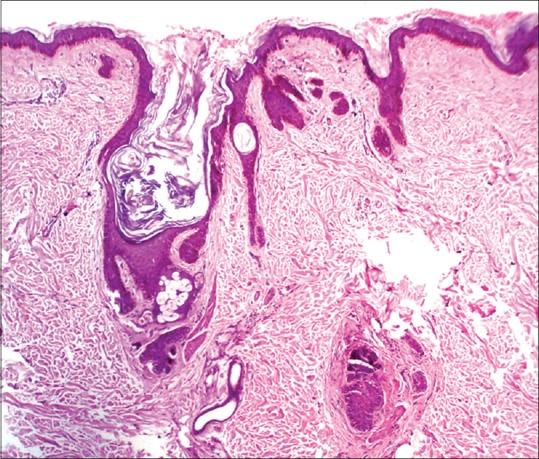

Dermoscopy of Nevus Comedonicus.

Vora Rita V, Kota RahulKrishna S, Sheth Niral K

Indian Dermatol Online J. 2017 Sep-Oct;8(5):388-389. doi: 10.4103/idoj.IDOJ_430_16.